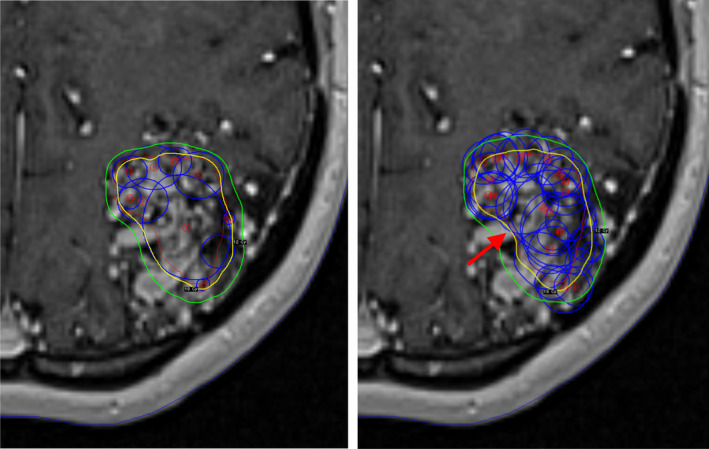

Figure 1 shows an example of manual and inverse plans for case number 6 in LGP showing all isocentres. Imported plans created by IntuitivePlan present themselves like all other plans in LGP and theoretically could be modified in that environment if desired. Apart from slight renormalizations (changes in the prescription isodose), plans have been used as calculated by IntuitivePlan.

Fig. 1.

Transaxial T1 weighted magnetic resonance imaging slices with the manual (left) and inverse (right) plans for case number 6. The blue circles denote the isocentre size and position. The 18 Gy (prescription dose) and 12 Gy isodose lines are shown in yellow and green respectively. The improved concavity of the prescription isodose (red arrow) on the medial edge of target is shown on the inverse plan.

Figure 1 shows the example of the manual and IntuitivePlan treatment plans for case number 6 in GammaPlan with all isocentres (shots) displayed. The large number of isocentres used in an IntuitivePlan may appear alarming to experienced Gamma Knife users who are often trained to avoid using too many isocentres. This is partly because more isocentres are associated with a longer beam on time. Despite IntuitivePlans having on average almost four times as many isocentres, the beam on time was only 18% higher. Overall treatment time, which includes movement between isocentres has not been evaluated. For the Gamma Knife Perfexion/Icon, movement takes approximately 3 s between each isocentre, so the increase in the mean number of isocentres from 10.8 for the manual plan to 40.4 for the IntuitivePlan corresponds with a modest increase of just under one and a half minutes in treatment delivery time. Often, the use of a large number of small isocentres can lead to a better dose gradient, but in this study we did not see this effect. The GI was slightly worse (larger) for the IntuitivePlan plans, though this was not statistically significant.